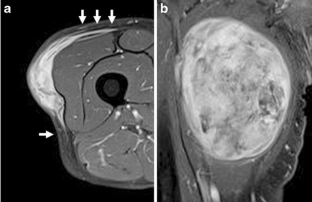

Fig. 1